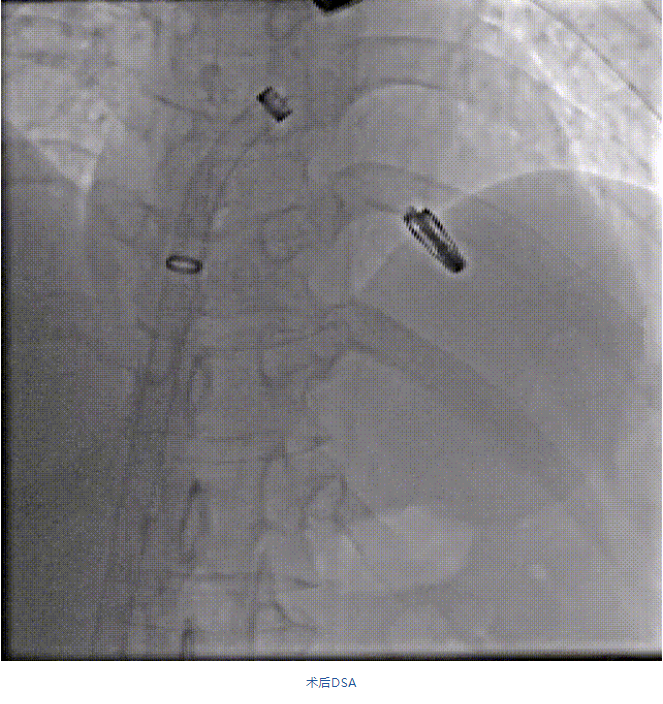

在阜外醫(yī)院潘湘斌教授團(tuán)隊(duì)的支持下,手術(shù)經(jīng)股靜脈-房間隔入路,采用全身麻醉插管,在TEE和DSA引導(dǎo)下完成房間隔穿刺。置入JensClip瓣膜夾系統(tǒng)后,在左房調(diào)整瓣膜夾的位置和軸向,后進(jìn)入左室,在TEE引導(dǎo)下捕捉二尖瓣前后瓣葉,并關(guān)閉瓣膜夾。經(jīng)TEE反復(fù)確認(rèn)手術(shù)效果后最終鎖定并釋放瓣膜夾。術(shù)后即刻超聲顯示瓣膜夾位置穩(wěn)定,功能良好,二尖瓣反流由術(shù)前4+減少至微量,手術(shù)圓滿成功。